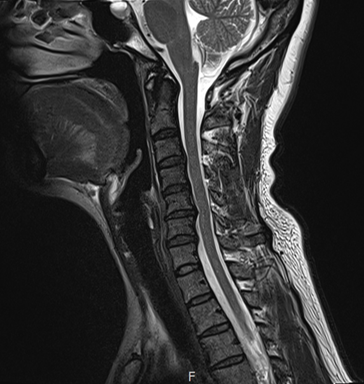

MRI 결과가 나왔을 때, 저는 '역시...' 했어요.

그림12.png

<Fig 1. 목 mri>

✔️ 경추 4-5-6번 사이에 협착증이 있었고

✔️ 주변 신경이 눌리고 있는 상태였어요

반면 뇌 MRI는 특별한 이상이 없었고요.